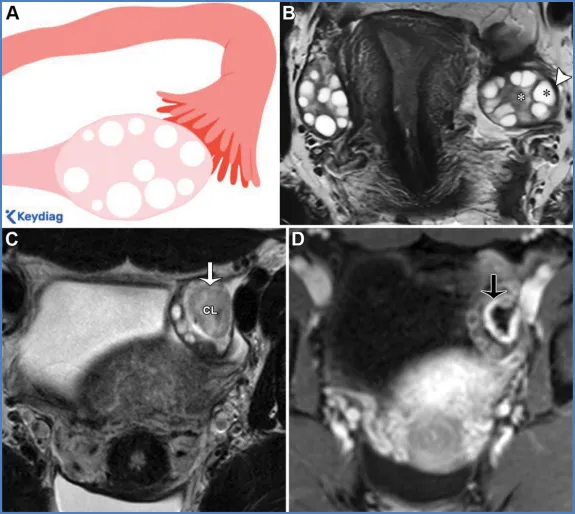

卵巢——卵巢是可活动的腹膜内器官,由卵巢韧带(连接卵巢与子宫角)、卵巢系膜(将卵巢固定于阔韧带)和悬韧带(连接卵巢与盆腔侧壁并包裹性腺血管)支撑(图6)(36)。性腺动脉起源于肾动脉下方的腹主动脉;右侧性腺静脉汇入下腔静脉,左侧性腺静脉汇入左肾静脉。性腺静脉直径大于0.8厘米为异常,尽管性腺静脉直径与静脉反流之间的相关性较差(37)。性腺血管走行于腰大肌前方、输尿管外侧。 卵巢的表现随月经周期阶段和绝经状态而变化。绝经前卵巢为较大的椭圆形结构,在T2加权成像上能清晰显示分区解剖结构,包括T2低信号的皮质、T2等信号的髓质(含疏松排列的基质和血管)、T2高信号的薄壁卵泡,偶尔可见黄体(19,38)。黄体因有黄素化的卵泡膜细胞而呈现T2等信号的厚壁,在退化过程中会变得锯齿状。非出血性黄体中央呈T1低信号、T2高信号,而出血性黄体中央呈T1和T2高信号,有时可见血细胞比容平面。静脉注射对比剂后,卵巢皮质和基质轻度强化,强化程度低于子宫肌层,而黄体壁则表现为早期明显强化(38)。绝经后卵巢比绝经前卵巢小,皮质和髓质呈T2等信号至低信号,偶尔可见小囊肿(38)。表S2以及图7-10详细描述了常见的生理性和其他良性卵巢表现的MRI特征(19,38-42)。图7. 两位不同患者的正常经前卵巢,突出显示了生理学观察结果。(A)示意图显示了带有卵泡的经前卵巢。(B)一位27岁女性患者的轴位T2加权图像显示一个椭圆形卵巢,具有T2低信号皮质(箭头)、T2等信号髓质(白色*)和多个T2高信号卵泡(黑色*)。(C、D)一位30岁女性患者的轴位T2加权(C)和对比增强脂肪抑制T1加权(D)图像显示了黄体(CL),这是经前女性常见的生理学表现。其影像学表现随发育阶段而变化。典型的黄体在T2加权成像上表现为囊性结构,中心呈高信号,壁厚且呈锯齿状,信号强度中等(C中的箭头),在静脉注射造影剂后明显强化(D中的箭头)。图8. 一名34岁闭经女性患者的多囊卵巢综合征与继发性非典型子宫内膜增生。(A)示意图展示了多囊卵巢,这是一种常见的内分泌疾病,影响高达10%的育龄女性。多囊卵巢综合征的诊断依据Rotterdam标准,该标准要求满足以下三项中的至少两项:多囊卵巢、月经稀发或无排卵,以及高雄激素血症。多囊卵巢的定义为:至少一侧卵巢的体积达到10毫升或以上,或者每个卵巢有20个或更多的卵泡(详见表S2)。(B)轴位T2加权图像显示双侧多囊卵巢增大,中央为T2等信号基质(小*),周围有多个T2高信号卵泡。(C)矢状位T2加权图像显示子宫内膜腔内呈不均匀的T2等信号(大*),对应活检证实的非典型子宫内膜增生。在所有增强后序列(包括延迟图像,未显示)中,非典型子宫内膜增生的强化程度低于子宫肌层,这与子宫内膜癌的强化模式相似。图9. 一名27岁女性患者的右侧卵巢扭转,该患者表现为急性盆腔疼痛。轴位T2加权图像显示右侧卵巢(RO)增大且水肿,伴有外周卵泡(箭头所示)。与正常的左侧卵巢(*)相比,右侧卵巢位置异常,位于子宫(U)的中央后方。卵巢扭转的其他表现(未显示)可能包括血管蒂扭转以及强化程度不一,这取决于缺血程度或是否存在梗死。图10. 一位43岁女性患者的输卵管卵巢脓肿,该患者在子宫内膜活检后出现恶心、呕吐和盆腔疼痛症状。轴位T2加权像(A)和对比增强脂肪抑制T1加权像(B)显示左侧附件区有一个多房囊性肿块。该肿块内含有脓性液体,在T2加权像上表现为不同的信号强度(A中的*),并具有增厚的强化壁以及多个强化分隔(B中的箭头)。高b值扩散加权像和ADC图(未显示)显示扩散受限,与脓液的存在相符。经皮引流后获得的细菌培养结果显示大肠杆菌阳性。——输卵管从子宫角延伸至卵巢(39)。近端的壁内部分穿过子宫肌层;远端带有伞端的漏斗部开口于卵巢附近的腹膜腔。输卵管被阔韧带的输卵管系膜包绕(图6)。在MRI上,它们表现为卵巢和子宫之间的T2低信号管状结构。子宫体和宫颈解剖。——子宫由子宫体和宫颈组成,宫颈下段(或子宫颈外口部)突入阴道上部(图2、3)(24、25、43)。在T2加权成像上,绝经前子宫的子宫体(子宫内膜、结合带和外肌层)和宫颈(宫颈管、宫颈内间质和宫颈外间质)均显示出清晰的分区解剖结构。绝经后或接受放射治疗后,这种分区解剖结构会变得不清晰(24、25、43)。子宫内膜腔由均匀的T2高信号子宫内膜衬里,延伸至同样为T2高信号的宫颈管(38)。子宫内膜厚度在子宫矢状面中部沿子宫长轴测量,其数值会随绝经状态和月经周期阶段而变化(表S3)(38、44-49)。对于有绝经后出血的患者,子宫内膜厚度≥5mm为异常;而无症状患者的阈值则不太明确(50)。结合带(子宫内肌层)呈T2低信号,向尾侧延续为T2低信号的宫颈内纤维间质。子宫外肌层呈T2等信号,过渡为宫颈外间质的T2等信号。正常结合带厚度≤8mm,若无微囊肿则可达11mm(45)。 子宫峡部是子宫体与宫颈之间的过渡区,在矢状位T2加权成像上表现为局限性缩窄,在轴位斜向T2加权成像上可见子宫血管进入(图2、3)(24、25)。宫颈内口和外口分别是宫颈管的上下开口。宫颈围绕宫颈管,包括上皮衬里和宫颈间质(43)。宫颈上段由腺状柱状上皮覆盖,宫颈下段(包括子宫颈外口部)由鳞状上皮覆盖。鳞状上皮与柱状上皮的交界处(鳞柱交界)在生育年龄具有动态变化,是大多数宫颈癌前病变和宫颈癌的起源部位。宫旁组织由主韧带和宫骶韧带构成,从宫颈两侧延伸至盆侧壁,包绕子宫血管、神经和输尿管(图2、3)。表S3以及图11-13概述了常见的子宫体和宫颈良性病变的MRI特征(38、44-49)。图11. 一位50岁女性患者的子宫内膜息肉,该患者在乳腺癌切除术后接受他莫昔芬治疗。(A)子宫矢状面示意图显示息肉状子宫内膜病变,伴有因子宫内膜腺体扩张而形成的囊性病灶。(B)冠状斜位T2加权像显示子宫内膜内有一个带蒂病变,具有T2低信号的纤维血管核心(白色箭头)和T2高信号病灶(黑色箭头),这些表现提示为子宫内膜息肉。通常可见明显的强化,与子宫肌层的强化程度相似(未显示)。明确诊断需要宫腔镜下切除,因为子宫内膜息肉、增生和肿瘤可能同时存在,且在影像学特征上可能重叠。偶然可见子宫腺肌症,表现为结合带内存在微囊肿(箭头所示)。图12. 弥漫性和局灶性子宫腺肌病(或子宫腺肌瘤)。(A)子宫矢状面中部的插图显示了弥漫性子宫腺肌病(上图)与局灶性子宫腺肌病或子宫腺肌瘤(下图)的对比。(B、C)两名不同的月经过多患者的矢状位T2加权图像显示,T2低信号的交界区(JZ)弥漫性增厚,伴有散在的T2高信号微囊肿(B中的实线),以及前部交界区伴有微囊肿的局灶性肿块样不对称增厚(C中的虚线)。这些表现是由于子宫肌层内存在异位子宫内膜腺体和间质(微囊肿)以及反应性平滑肌增生(交界区增厚)所致。图13. 纳博特囊肿与隧道簇。插图(A)及两名不同患者的子宫正中矢状面T2加权图像(B、C)显示,浅层宫颈基质内的单房囊肿为典型的纳博特囊肿(A图左图;B图),而向宫颈基质深部延伸的多房囊肿为隧道簇的特征性表现(A图右图;C图)。务必在增强图像上排除强化实性组织的存在(未显示),因为多房性宫颈病变中若出现强化实性组织,应怀疑宫颈胃型腺癌。可能需要进行宫颈锥形活检以明确诊断。子宫在骨盆内的位置会因膀胱充盈程度和盆腔瘢痕情况而有所不同。倾位指的是宫颈与阴道之间的角度:前倾位是向前倾斜,后倾位是向后倾斜(图14)(38)。屈曲描述的是子宫体与宫颈之间的角度:前屈是向前弯曲,后屈是向后弯曲(38)。图14. 插图(A)和磁共振图像(B、C)显示了女性骨盆内子宫的各种位置。子宫倾(Version)指的是宫颈与阴道之间的角度:A中的上组插图将该角度显示为黄线相对于红线的倾斜度。前倾(Anteversion)指向前倾斜,后倾(Retroversion)指向后倾斜。子宫屈(Flexion)描述的是子宫体与宫颈之间的角度:A中的下组插图将该角度显示为蓝线相对于黄线的倾斜度。前屈(Anteflexion)指向前弯曲,后屈(Retroflexion)指向后弯曲。两名患者的矢状位T2加权图像(B、C)中,B显示的是前倾前屈位子宫,C显示的是后倾后屈位子宫。阴道是一个纤维肌性结构,通过膀胱阴道隔与膀胱相隔,通过直肠阴道隔与直肠相隔(图4)(51)。在轴位T2加权成像上,绝经前阴道通常呈H形或W形塌陷,具有高信号的黏膜皱襞和低信号的壁。绝经后,皱襞消失,阴道壁厚度变薄。阴道上部有由突出的宫颈形成的穹窿,阴道下部通过阴道口开口于外阴前庭。表S4和图15详细描述了常见良性阴道病变的MRI特征(51-53)。图15. 四个不同患者的矢状面示意图(A)和轴位T2加权图像(B–E)显示了阴道囊肿、斯基恩氏腺囊肿以及尿道憩室。巴氏腺囊肿:位于耻骨联合处或其下方阴道后外侧壁的单房囊肿(A中的灰色椭圆形,B中的T2高信号囊性病变)。加特纳管囊肿:位于耻骨联合处或其上方阴道前外侧壁的单房囊肿(A中的蓝色椭圆形,C中的T2高信号囊性病变)。斯基恩氏腺囊肿:位于耻骨联合下方、阴道前方、尿道下段外侧的单侧或双侧小单房囊肿(A中的浅黄色椭圆形,D中的T2高信号囊性病变)。尿道憩室:在耻骨联合附近,尿道中远端后外侧出现的圆形、椭圆形或U形T2高信号液性囊袋状突起(A中的尿道囊袋状突起)。在罕见情况下,尿道憩室可能完全环绕尿道(E中的T2高信号环形囊性病变)。外阴由女性外生殖器组成(图16)(53)。阴阜位于耻骨联合前方,由脂肪组织构成。大阴唇是位于阴阜下方并与其相连的厚皮肤皱襞。小阴唇是大阴唇之间较薄的皱襞,向前会合于阴蒂头。小阴唇之间的前庭包含尿道外口(尿道口)和阴道口(阴道开口)。图16. 示意图(A)和轴位T2加权图像(B)显示了外阴区域或女性外生殖器。阴阜位于耻骨联合前方,由脂肪组织构成。大阴唇是位于阴阜下方且与其相连的厚皮肤皱襞。小阴唇是大阴唇之间较薄的皱襞,向前汇聚于阴蒂头。小阴唇之间的前庭前部有尿道外口(尿道口),后部有阴道口(阴道开口)。参考文献:https://doi.org/10.1148/rg.250029